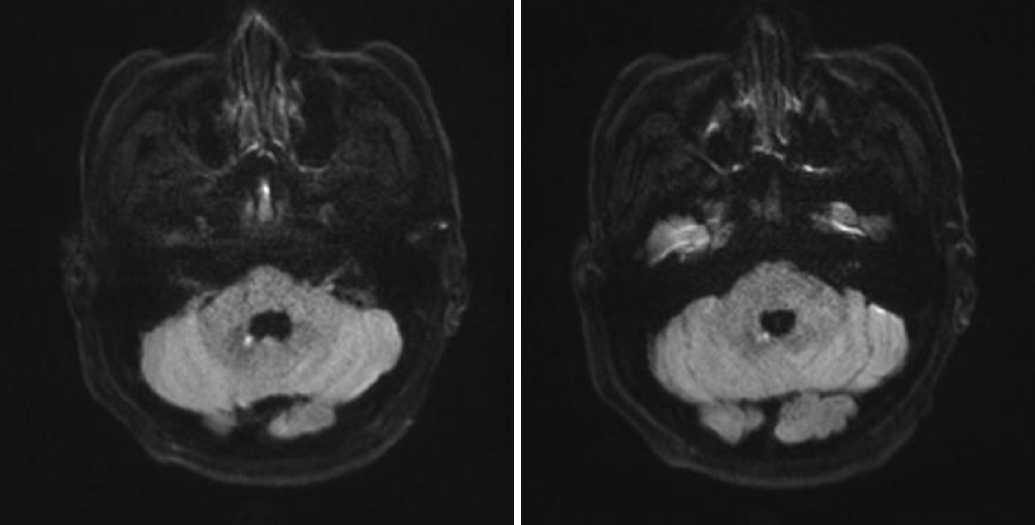

3차원 비디오안구운동검사(video-oculography) (SMI, Teltow, Germany; resolution of 0.1º, a sampling rate of 60 Hz)에서 우측으로의 자발안진이 관찰되었다(Fig. 1-A). Dix-Hallpike검사에서는 방향변화땅방향수평안진을 나타냈다. 우측 Dix-Hallpike검사에서 환자는 우측으로의 수평안진을 보였고(Fig. 1-B), 좌측 Dix-Hallpike 검사에서는 회선상방 성분과 함께 좌측으로의 수평안진을 보였다(Fig. 1-C). 양측에서의 수평안진은 최대서상속도가 6°/s로 대칭적이었다. 바로눕기검사에서(Fig. 1-D) 잠복기 없이 반시계 방향의 회선상방안진이 발생하여 자세를 유지하는 동안 지속되었다. 양측으로의 머리회전검사(앙와위회전검사)에서 잠복기 없이 우측으로의 수평안진이 발생하여 15-20초간 지속되었다. 머리충동검사(head impulse test)와 양온도안진검사(bithermal caloric test)는 정상 소견을 보였다. 시운동성안진검사(oculomotor test)에서 수평신속보기운동(horizontal saccade)과 원활추종운동검사(smooth pursuit eye movement)는 정상 소견을 보였다. 환자는 정현파회전검사(sinusoidal harmonic acceleration)에서 정상 이득(gain)과 위상(phase)의 전정안구반사(vestibulo- ocular reflex)를 보였으며, 등속회전검사(step velocity rotations)에서 회전전안진(pre-rotatory nystagmus)과 회전후안진(post-rotatory nystagmus)의 정상 시간상수(time constants)를 보였다. 경부전정유발근전위(cervical vestibular evoked myogenic potentials) 및 안구전정유발근전위(ocular vestibular evoked myogenic potentials)는 정상 파형이 대칭적으로 나타났다. 주관적시수직검사(subjective visual vertical test)는 시행하지 못하였으며, 안저촬영 상 우안의 회선은 저명하지 않았지만 좌안의 외회선이 관찰되었다. 뇌 자기공명영상에서 우측 치아핵 내측 경계의 배쪽 구역에 국소 경색이 확인되었다(Fig. 2). 현기증 증상은 서서히 호전되었으며 1개월 후 외래 진찰에서 환자는 더 이상 어지럼을 호소하지 않았으며 안진도 관찰되지 않았다.